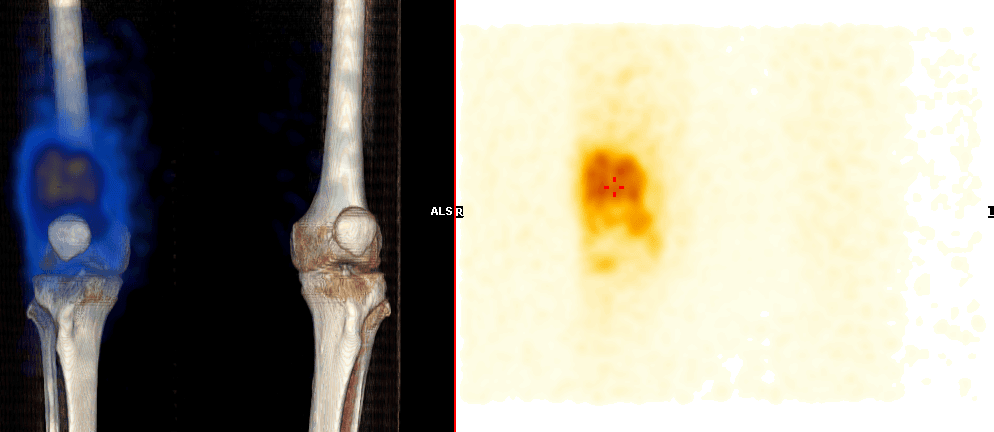

- Kontrola distribuce: postinjekční scintigrafie k ověření správné intraartikulární aplikace.